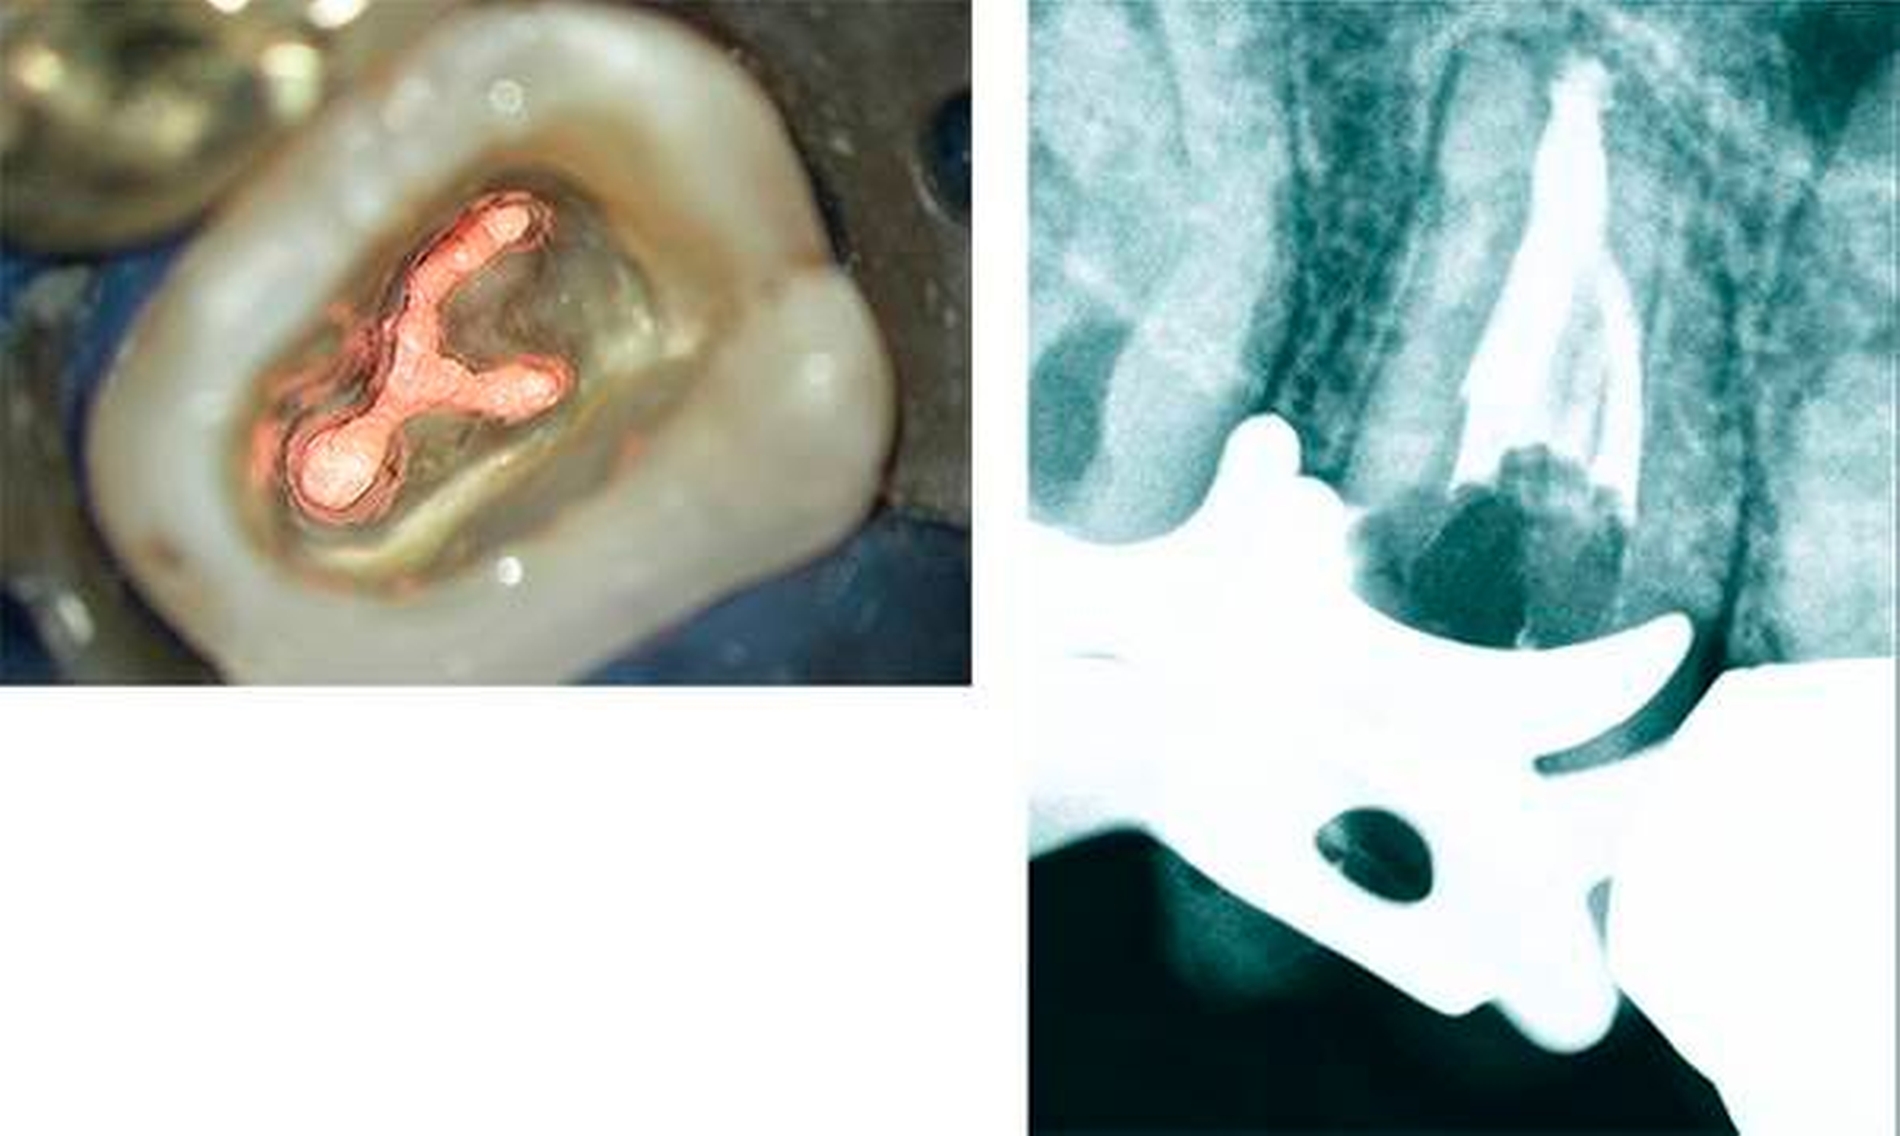

Im Fall eines einwurzeligen oberen ersten und zweiten Molaren kann ein sogenanntes c-förmiges Wurzelkanalsystem auftreten. Diese – im Ergebnis einer unvollständigen Wurzelteilung entstandenen – Strukturen können von sich von bukkal nach palatinal erstrecken oder von mesial nach distal (Abbildungen 15 und 16).

Schließlich werden mit der mechanischen Erweiterung und konischen Ausformung der Wurzelkanäle die Voraussetzungen für einen dichten Verschluss des Wurzelkanalsystems geschaffen, damit eine Rekolonisierung von endodontischen Hohlräumen vermieden werden kann (Abbildung 7) [Klimm, 2003; Hülsmann & Schäfer, 2005]. Im Ergebnis einer vollständigen antimikrobiellen Therapie bilden sich ausgedehnte periapikale Aufhellungen und pathologische Prozesse der Kieferhöhle vollständig zurück und erfordern keinen weiteren chirurgischen Eingriff (Abbildung 8).